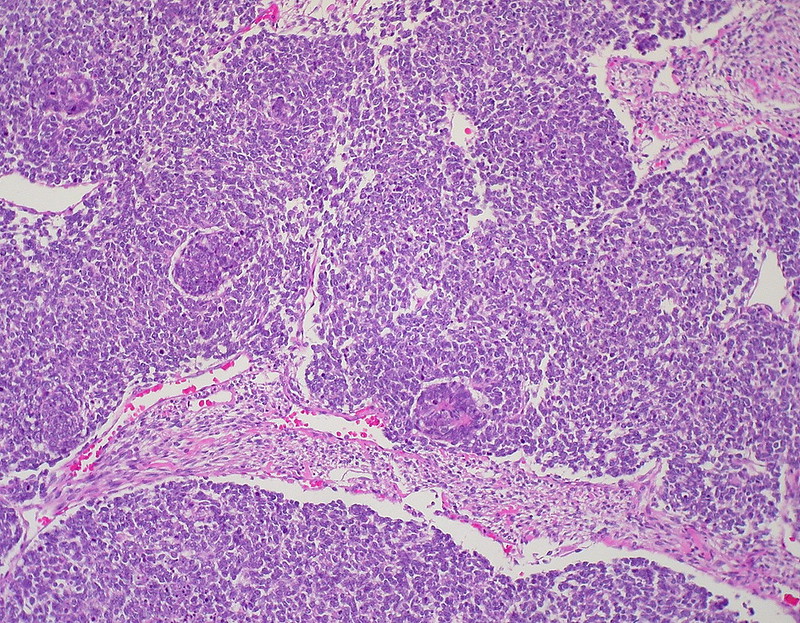

Wilms Tumor

Wilms tumor is a malignant kidney tumor composed of primitive glomeruli, tubules, and stromal cells blastema which is an immature kidney mesenchyme.

Wilms tumor is associated with WT1 mutation, especially in syndromic cases.